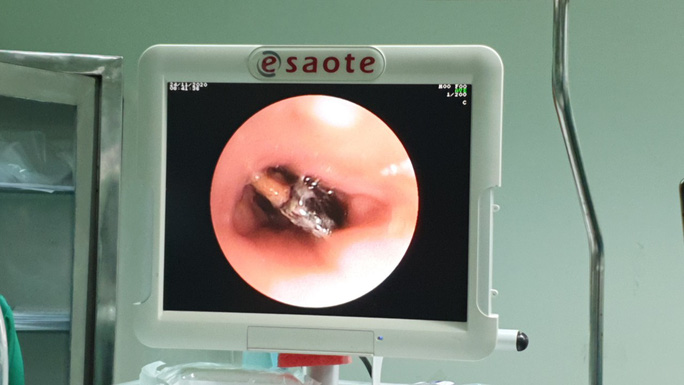

Hình ảnh hạt hồng xiêm lúc nội soi và lúc được lấy ra ngoài

Sau khi nhập viện tại Khoa Hô hấp của Bệnh viện Đa khoa trung ương Cần Thơ, các bác sĩ thăm khám kết hợp với kết quả CTSan ngực cho thấy hình ảnh dãn phế quản và viêm thùy dưới phổi phải, có hình ảnh dị vật nhánh phế quản thùy dưới phổi phải. Bệnh nhân được chỉ định nội soi phế quản thám sát ghi nhận niêm mạc phế quản nhiều giả mạc, có một dị vật nằm trọn lòng phế quản phân thùy dưới phổi phải bị che lấp bằng giả mạc và niêm mạc phù nề.

Các bác sĩ dùng kềm lấy dị vật nhưng chỉ lấy được phần gai của hạt hồng xiêm. Sau đó, bệnh nhân được điều trị tích cực nội khoa nhằm giảm phù nề và được nội soi lần 2.

Ngày 23-11, hội chẩn liên khoa tiến hành nội soi phế quản ống mềm lần thứ hai có sử dụng tiền mê cho thấy hạt hồng xiêm nằm ngang trong lòng phế quản phân thùy dưới phổi phải. Trong 150 phút căng thẳng, các bác sĩ dùng thòng lọng kéo được hạt hồng xiêm ra ngoài.